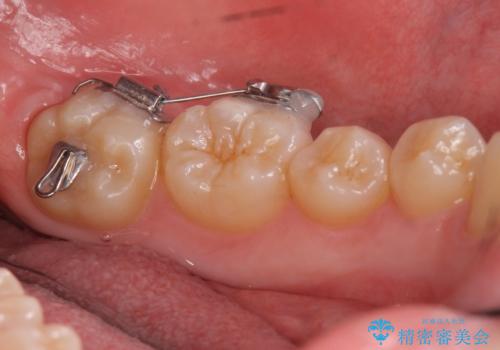

- 歯のがたつきを主訴に来院。

左右とも奥歯のがたつきがあり、左奥はすれ違っていました。

また、右奥は反対咬合になっていました。

患者様が気づかない範囲で妥協して終わるということをせず、しっかり奥歯に部分矯正を用いて大きな問題を解決してからインビザライン治療に入りました。

奥歯のワイヤー部分矯正は位置的に人から気づかれることはないと思います。